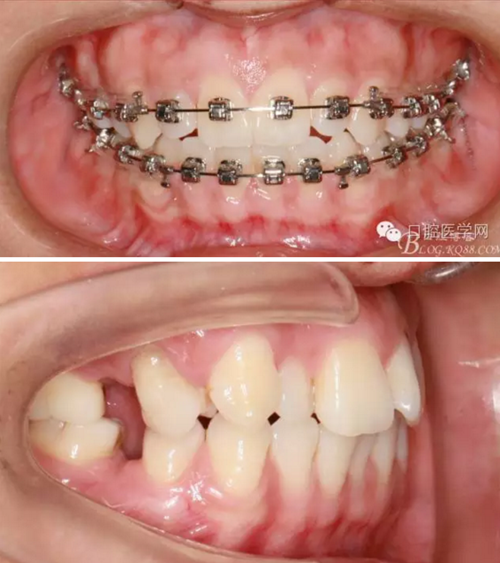

37,45缺失后,鄰牙近中移動(dòng)占據(jù)了部分牙位;患者要求減少治療費(fèi)用,不做種植修復(fù),那怎么協(xié)調(diào)右側(cè)的咬合關(guān)系?

15是根管治療過(guò)的牙齒,只好忍痛舍去......

在滿足功能的前提下,退而求其次...有時(shí)候,正畸醫(yī)生不得不妥協(xié)。